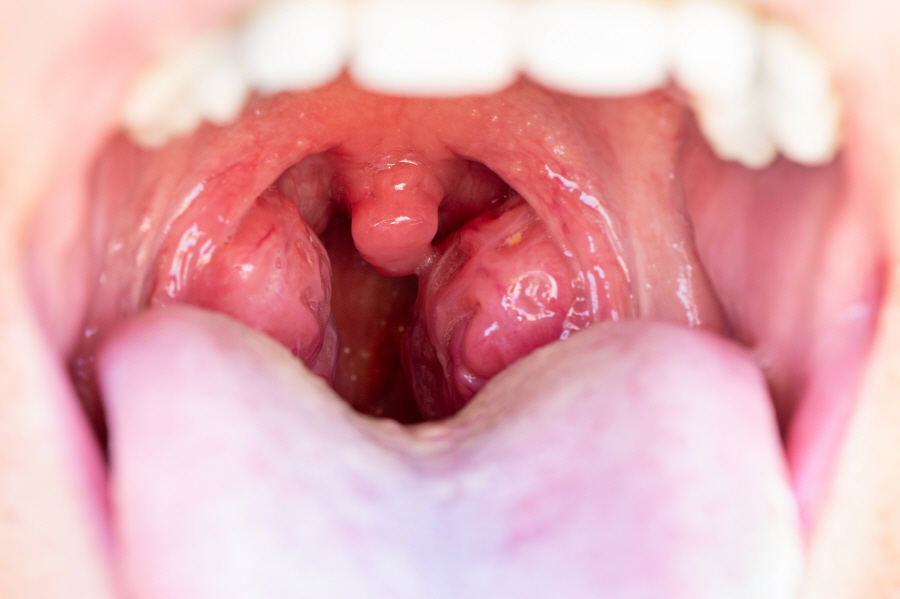

편도선염은 목 안쪽 양옆에 위치한 편도에 염증이 생기는 질환이에요.

주요 증상으로는 인후통, 발열, 삼킬 때 통증, 편도의 붓기와 발적, 그리고 하얀 고름이 생길 수 있어요.

편도선염은 목구멍 양쪽에 위치한 편도가 감염으로 인해 붓고 염증이 생기는 질환이에요.

| 편도 부종 | 편도가 붓고 빨갛게 변하며, 경우에 따라 고름이 보일 수 있어요. |